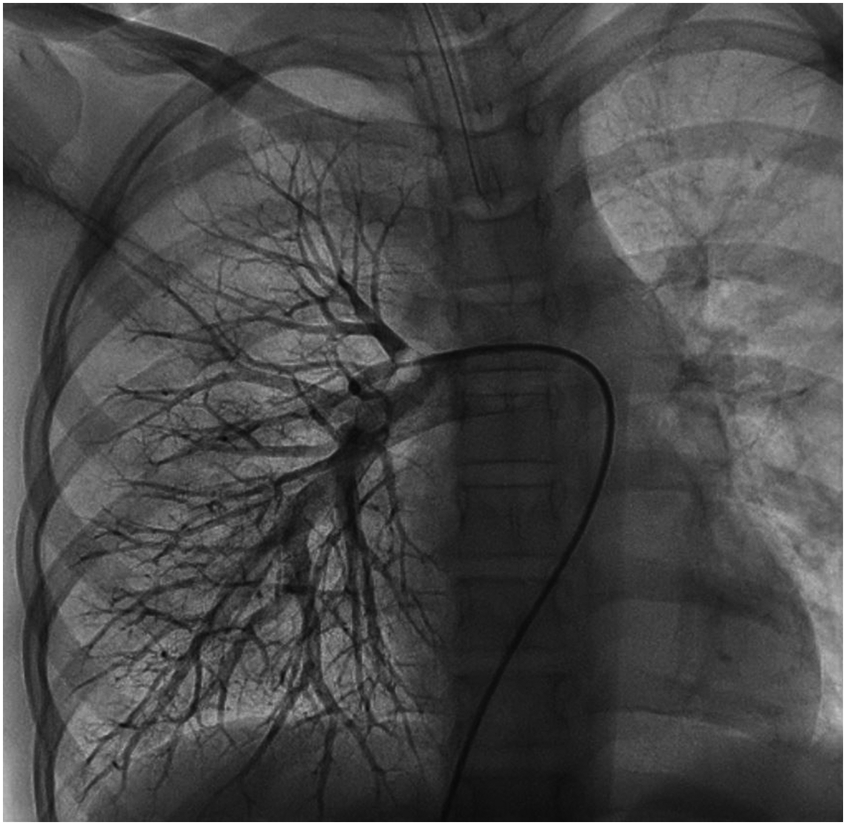

We performed a detailed evaluation of the cardiovascular system, including tests for right-to-left diverged heart disease, pulmonary arteriovenous fistula, severe valve regurgitation, and pulmonary hypertension.After conducting detailed echocardiography and cardiac CTA, we performed cardiac catheterization. The results of cardiac catheterization were negative. Cardiac catheterization findings are shown in Figures 3–6. We were unable to find a shunt at the atrial, ventricular, or aortic levels. The child's echocardiogram and cardiac macrovascular CT results were normal, ruling out complex congenital heart disease such as pulmonary atresia.

Figure 6

Frontal views of the child's right pulmonary arteriogram. No pulmonary arteriovenous fistula was found.